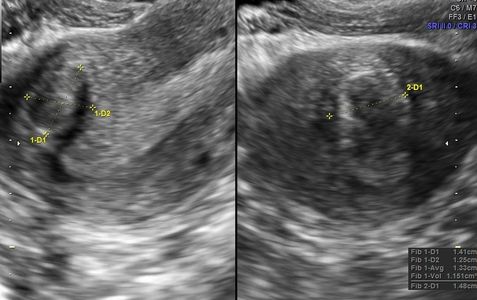

Fibroids appear as discrete structures in the wall of the uterus, although sometimes they grow into the uterine cavity. Fibroids closest to the uterine cavity (endometrium) are most likely to cause symptoms of bleeding. Types of Fibroids

Adenomyosis typically presents with an enlarged uterus. The myometrium is thickened and non-uniform (heterogeneous) with a 'streaky' appearance. Fibroids are often absent, but co-existing fibroids are not unusual.